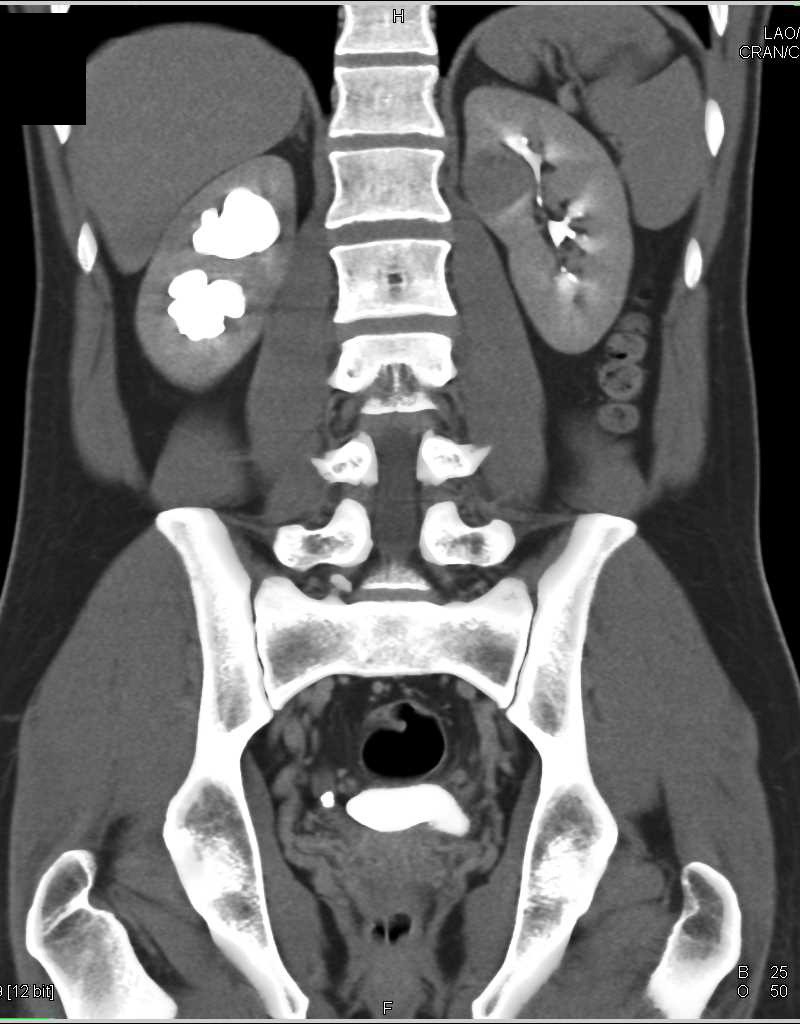

Papillary Renal Cell Carcinoma Left Kidney and Stone Distal Right Ureter with Obstruction